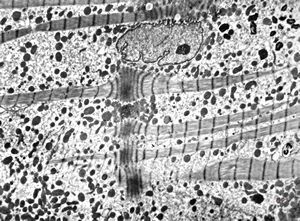

normal cardiomyocyte … longitudinal section(N - nucleus, m … mitochondria, f - myofilaments)

normal cardiomyocyte … longitudinal section(m … mitochondrion, f - myofilaments, L … lipid droplets, arrows … tubulesof sarcoplasmic reticulum)